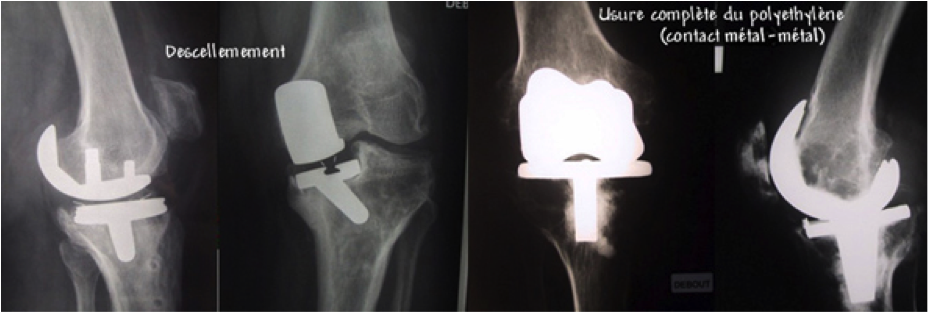

Descellement (que la prothèse ait été posée avec ou sans ciment) : sans cause apparente ou parfois en cas de surcharge pondérale ou de sur utilisation de la prothèse (c'est pourquoi on la réserve plutôt aux sujets âgés). Ce descellement peut conduire à un remplacement de la prothèse avant le délai prévu initialement.

Usure de la prothèse : cette usure se produit toujours bien qu'elle soit difficile à mesurer. Statistiquement, la durée de vie espérée est de 15 à 25 ans.

Elle est parfois réduite, rendant nécessaire le changement de la prothèse. Cela témoigne de la fiabilité actuelle des prothèses du genou même si ces chiffres sont très variables d'un patient à l'autre et sont influencés par le type de prothèse utilisé ( degré de contrainte +++).

A un stade avancé, une reprise chirurgicale est souvent indiquée. Celle ci est très variable (changement d’un insert en polyéthylène, changement d'une PUC pour une PTG, reprise d'une PTG par une autre).